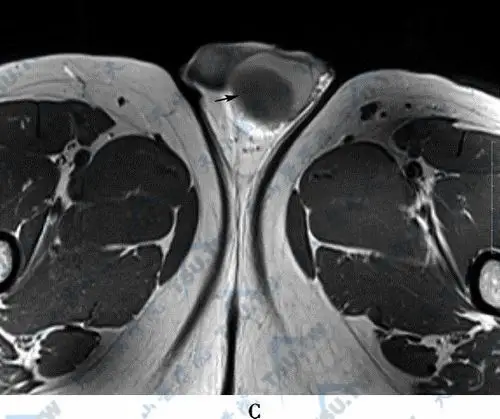

睾丸囊肿(testicle cyst)的ct与磁共振现象